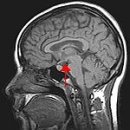

영역에 방사선 동위원소가 있는지를 관찰함으로써 뇌의 특정 영역이 다른 영역 보다 활성화되는 지를 볼 수 있다. PET는 fMRI와 비슷한 공간 해상도를 지니지만 시간 해상도가 너무 약하다. (시간 해상도는 움직이는 동영상에서 각 영상 프레임의 시간...